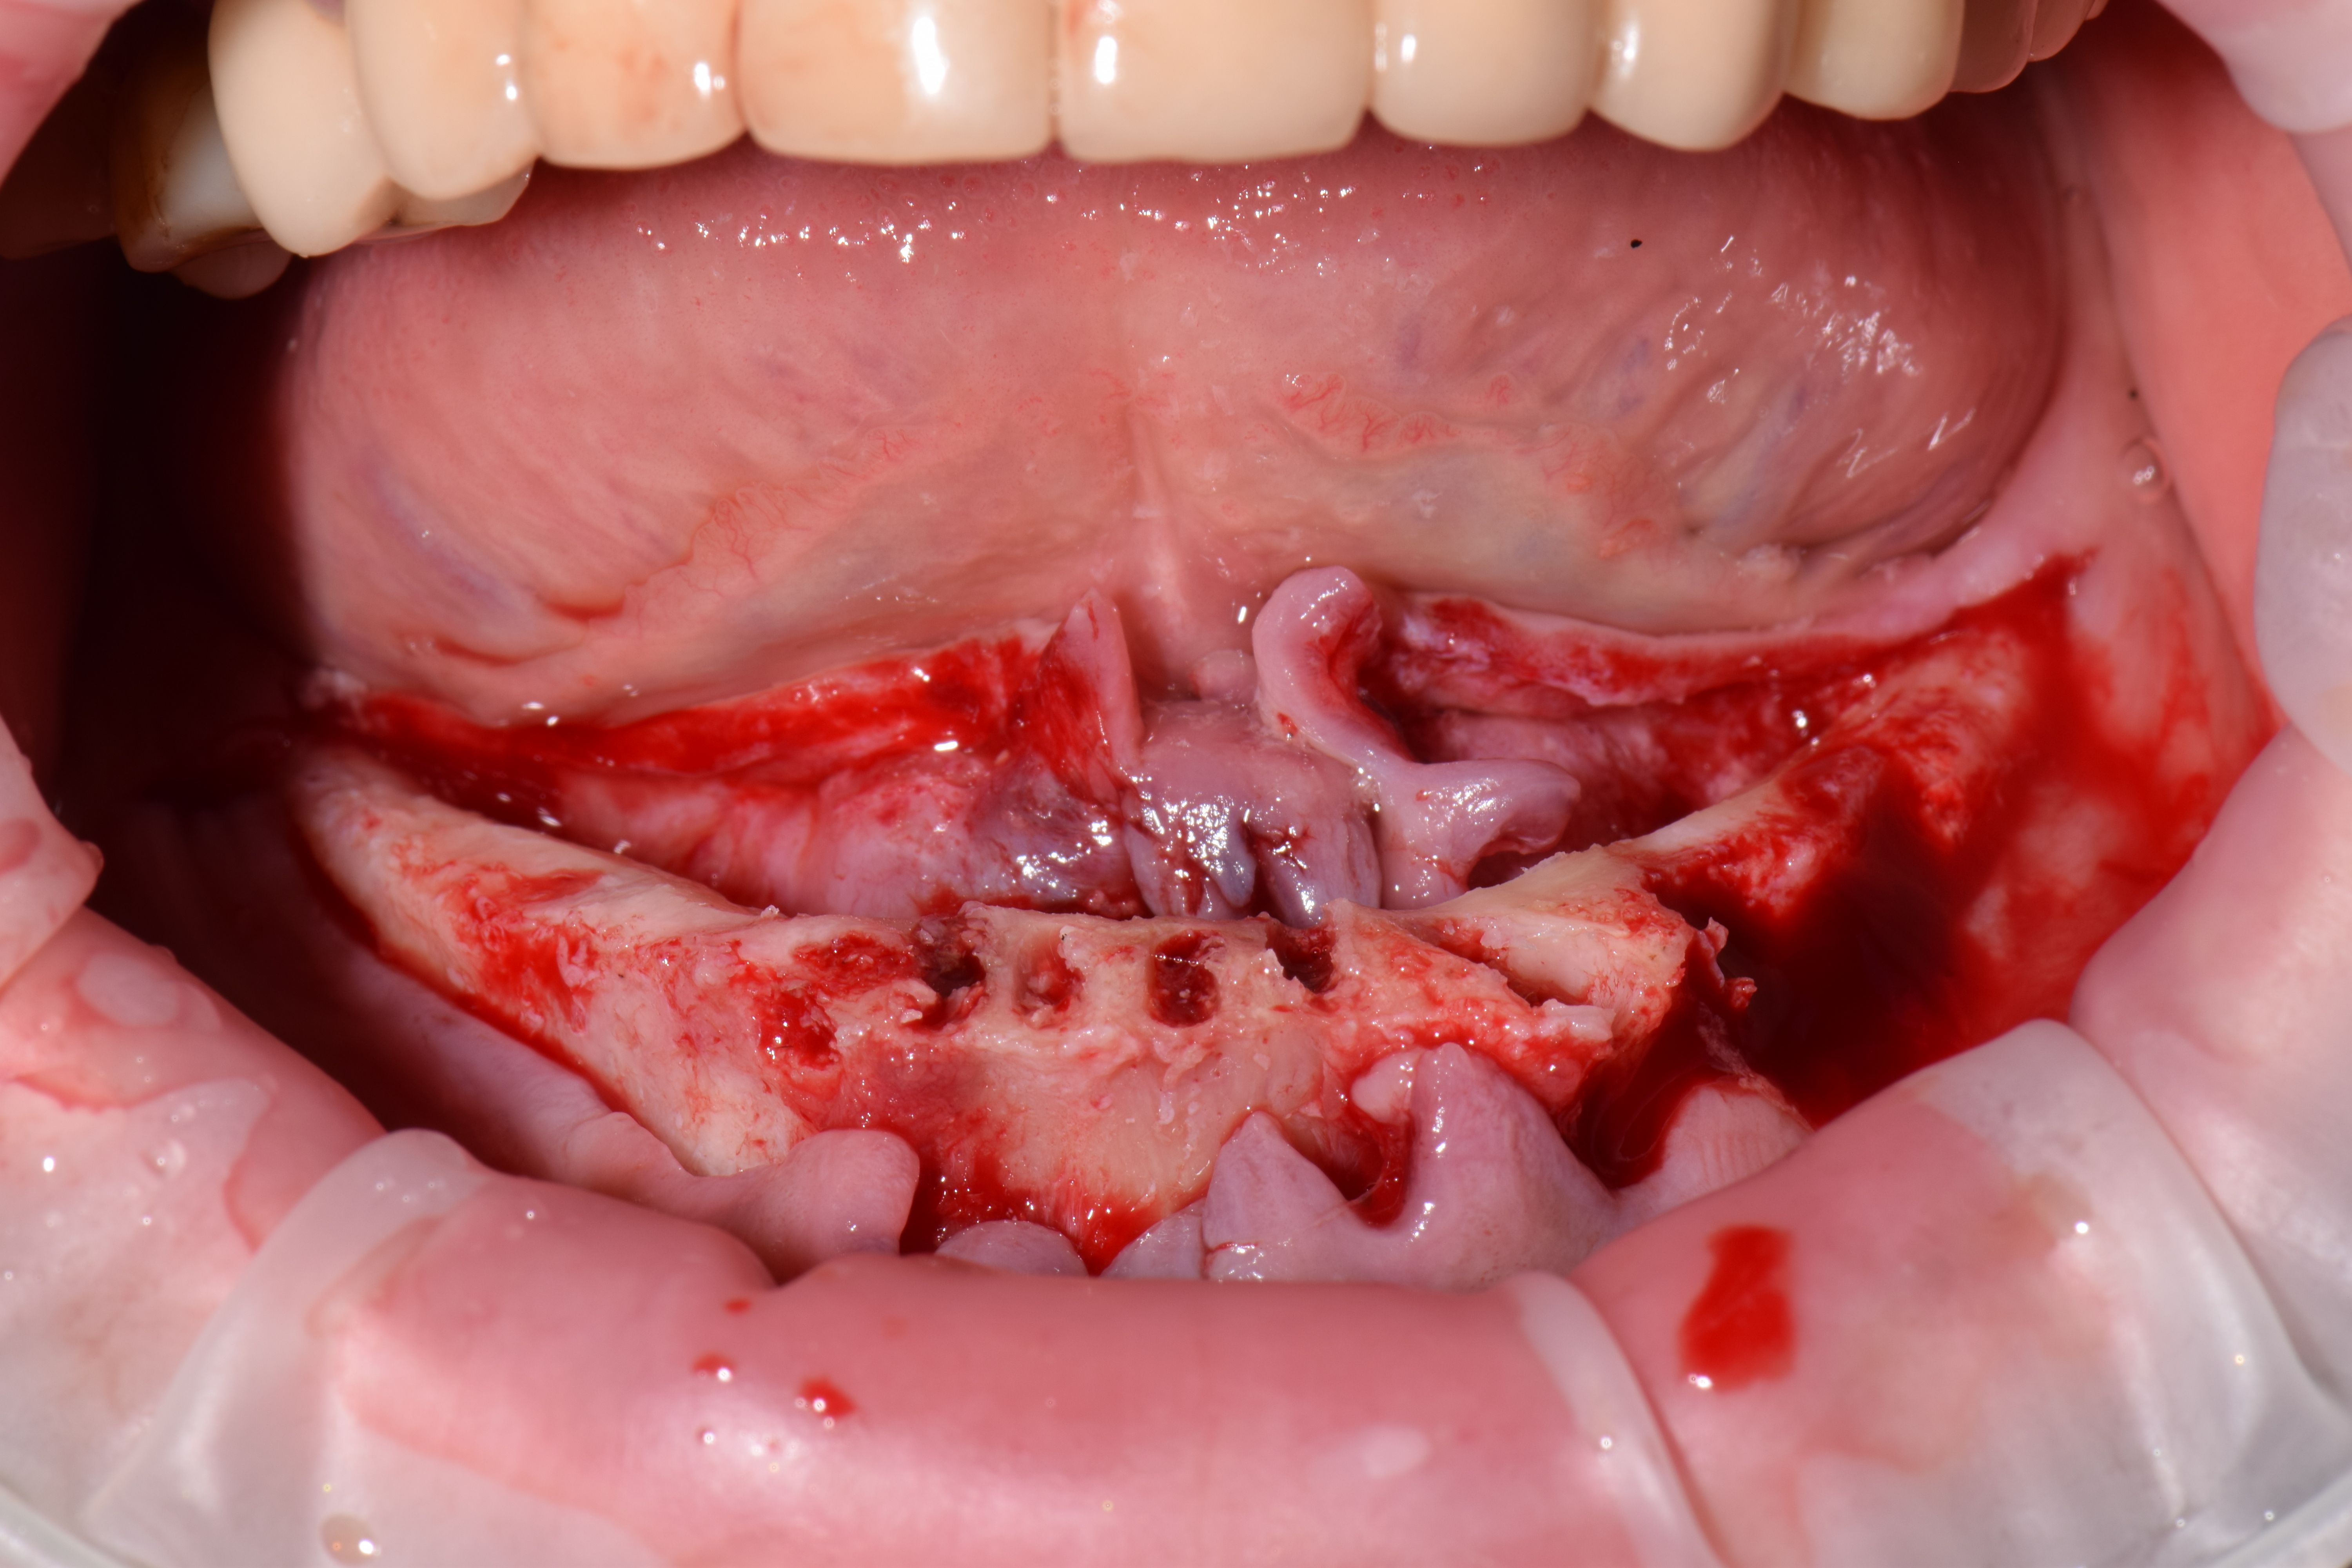

| ИМПЛАНТАЦИЯ |

|

|